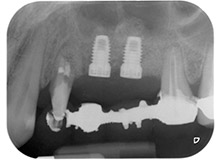

Después de la medicación tópica con un 25 % de gel de metronidazol (Elyzol) en las bolsas de la pieza 24, se inició un tratamiento causal de terapia periodontal con desinfección de toda la boca. El tratamiento ortógrado del canal radicular se revisó mediante una obturación con gutapercha termoplástica, un poste de fibra de vidrio y una acumulación de núcleo de composite (figura 2). El puente se recementó fuera de la oclusión para permitir la cicatrización sin problemas de los lugares de la GTR y la GBR.

Un mes después, en el día de la intervención, el dolor y la inflamación se habían reducido al mínimo en la pieza 24, pero seguía habiendo una movilidad de clase II de Miller. Después de la apertura de los colgajos y de la limpieza del tejido infectado periapical y perirradicular, la extensión del defecto óseo quedó evidente (figuras 2 y 3).